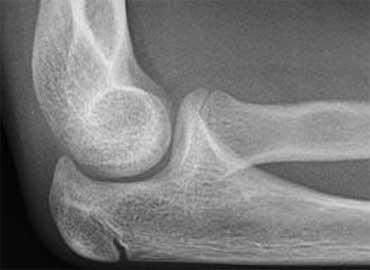

Positive Anterior Fat Pad sign. On digital radiographs you may need to adjust the window width and level to appreciate this. No fracture was visible on the X-rays.

Dấu hiệu đệm mỡ dương tính (2)

Bất kỳ sự giãn khớp khuỷu nào do xuất huyết, viêm hoặc chấn thương đều tạo ra dấu hiệu đệm mỡ dương tính.

Nếu không có dấu hiệu đệm mỡ dương tính ở trẻ em, tổn thương trong khớp đáng kể là khó xảy ra.

Dấu hiệu đệm mỡ có thể nhìn thấy mà không phát hiện được gãy xương nên được coi là gãy xương ẩn.

Những bệnh nhân này được điều trị như gãy xương không di lệch với nẹp bột trong 2 tuần.

Skaggs và cộng sự đã chụp X-quang lại sau ba tuần ở những bệnh nhân có dấu hiệu đệm mỡ sau dương tính nhưng không thấy gãy xương.

Họ tìm thấy bằng chứng gãy xương trong 75% trường hợp.

Họ kết luận rằng trong chấn thương, sự di lệch của đệm mỡ sau gần như là dấu hiệu đặc trưng bệnh lý của sự hiện diện gãy xương.

Tuy nhiên, sự di lệch của đệm mỡ trước đơn thuần có thể xảy ra do tràn dịch khớp tối thiểu và ít đặc hiệu hơn cho gãy xương.